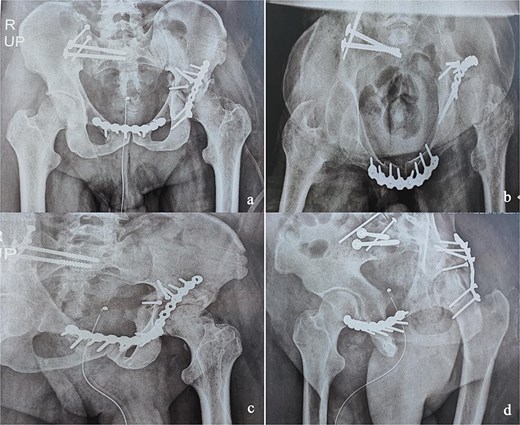

This was a 42-year-old male patient with no previous medical history who was admitted to the intensive care unit for treatment of polytrauma: severe chest trauma and pelvic trauma. During his stay in intensive care, the patient developed a pulmonary infection complicated by septicemia, requiring prolonged antibiotic therapy and thereby contraindicating any internal surgical fixation. After hemodynamic and respiratory stabilization, he was transferred to our department 40 days after the trauma with the following injuries: an unstable pelvic ring fracture classified as Tile-AO B1-2 [4]: disjunction of the pubic symphysis, disjunction of the right sacroiliac joint, and an ipsilateral crescent fracture classified as Kumar-Day 2 [5], along with a transverse–posterior wall fracture of the left acetabulum associated with a posterior dislocation of the hip, which was initially reduced but remained unstable. Fixation was performed using a Hoffmann II external fixator applied to the iliac crests with poor reduction (Fig. 1). He presented with complete weakness of the left foot dorsiflexors, with preserved sensation and no urogenital or abdominal complications. ORIF was performed in two stages, 5 days apart. The first stage consisted of performing the first two windows of the ilioinguinal approach: the lateral window to access the sacroiliac joint and the middle window to access the lower part of the sacroiliac joint and remove the osteofibrous callus. A Pfannenstiel approach was used to remove the callus at the pubic symphysis and fix it with a plate. The patient was then placed in the prone position and a posterior approach to the right sacroiliac joint was performed to carry out the same procedures on the posterior part of this joint and to perform fixation using ilioiliac and iliosacral screws. The second stage of the operation involved acetabular surgery. Given the chronic dislocation of the left hip, an anterior approach to the hip was performed to remove the intra-articular fibrosis facilitating the subsequent reduction of the femoral head. A Kocher-Langenbeck approach was then performed to remove the callus, reduce the femoral head and fracture, and fix it with a plate (Fig. 2). Postoperatively, the patient retained neurological deficits. At 6 months, the patient was able to walk without assistance and had a Harris Hip Score (HHS) score of 80 and Majeed score of 75 [6, 7].

(a) Anteroposterior pelvic X-ray showing delayed pelvic and acetabular fractures. (b) Anterior view of the pelvis on 3D section: pubic symphysis disjunction and right sacroiliac dislocation (arrows), transverse component of the left acetabular fracture (star). (c) Posterior view of the pelvis on 3D section: right crescent fracture associated with right sacroiliac dislocation (circles), fracture of the posterior wall of the left acetabulum associated with posterior dislocation of the femoral head (triangle). (d) Axial section of the pelvic CT-scan: right crescent fracture Kumar-Day 2 (green arrow).